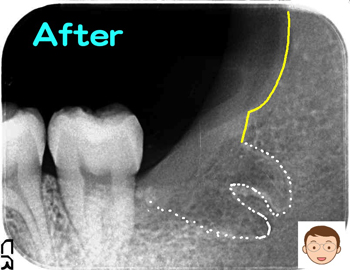

下アゴの骨(写真の黄色部)に取り囲まれていたり、歯の根が曲がり、骨を抱きかかえている(蟹ばさみ様)と、抜歯は難航します。今回、この条件が該当することに…。

当初、歯茎を切らずに抜歯を行う予定でしたが、なかなか抜けない理由を患者様に伝えました。歯茎を少し切らせていただくことで視野が広がり、抜歯がスムーズに行われました。抜歯開始から約25分、無事に完了。抜歯跡には、痛みの軽減と治癒の促進をねらってテルプラグを入れています。